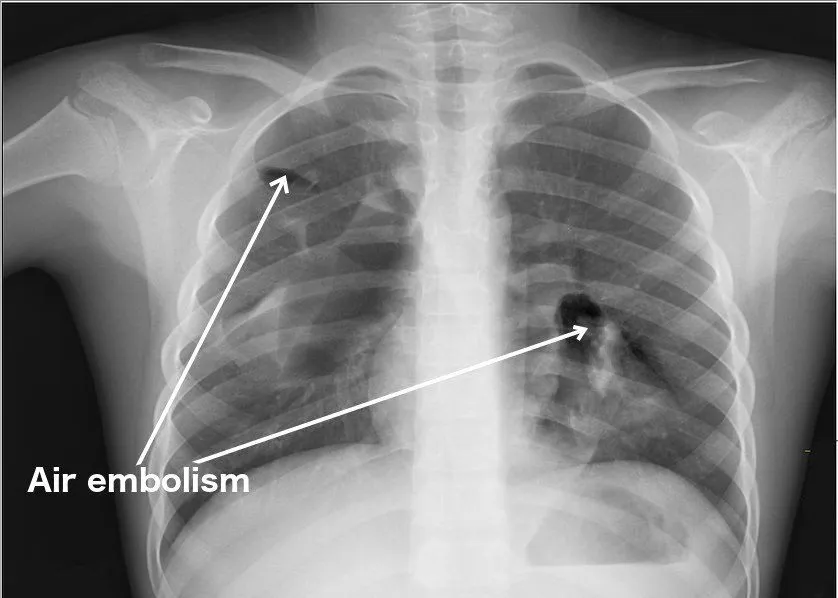

An air bubble in a blood vessel can cause an air embolism — an obstruction to blood flow. In adults, small bubbles (a few millilitres) injected into a vein are usually absorbed harmlessly, while larger volumes (roughly 100–300 mL of air, or about 5 mL per kg of body weight) entering the bloodstream can be fatal. The danger depends on the volume of air, where it lodges (heart, brain or lungs are the worst), and whether it reaches arteries directly. When an embolus blocks an artery in the lungs, it is called a pulmonary embolism.

An embolism has the capacity to completely cut off the blood supply to a particular organ. Therefore, if it occurs in the blood vessels of the heart, it can potentially cause a heart attack. In the brain, it can cause a paralytic stroke or even brain death. In the lungs, it can cause a pulmonary embolism.